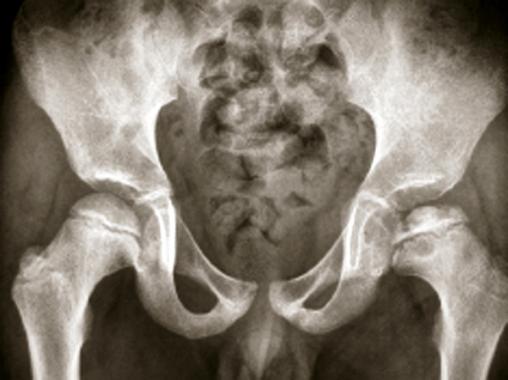

Ostéochondrite de hanche gauche à un stade plus avancé de fragmentation. L'os nécrosé commence à se résorber pour faire apparaître des îlots cartilagineux (en noir) au sein de l'épiphyse fémorale atteinte.